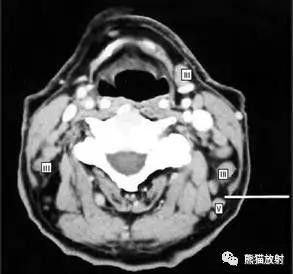

舌骨上水平CT增强图像

横白线在两侧颌下腺后缘。

线以前为I区淋巴结,线后为II区淋巴结。在颈内静脉附近为IIA区,颈内静脉后面不接近静脉的淋巴结为IIB区。